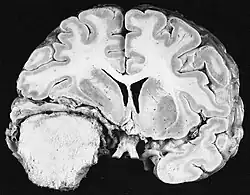

Radiation

Up to 10% of invasive cancers are related to radiation exposure, including both non-ionizing radiation and ionizing radiation.[9] Unlike chemical or physical triggers for cancer, ionizing radiation hits molecules within cells randomly. If it happens to strike a chromosome, it can break the chromosome, result in an abnormal number of chromosomes, inactivate one or more genes in the part of the chromosome that it hit, delete parts of the DNA sequence, cause chromosome translocations, or cause other types of chromosome abnormalities.[87] Major damage normally results in the cell dying, but smaller damage may leave a stable, partly functional cell that may be capable of proliferating and developing into cancer, especially if tumor suppressor genes were damaged by the radiation.[87] Three independent stages appear to be involved in the creation of cancer with ionizing radiation: morphological changes to the cell, acquiring cellular immortality (losing normal, life-limiting cell regulatory processes), and adaptations that favor formation of a tumor.[87] Even if the radiation particle does not strike the DNA directly, it triggers responses from cells that indirectly increase the likelihood of mutations.[87]

Ionizing radiation

Sources of ionizing radiation include medical imaging, and radon gas. Ionizing radiation is not a particularly strong mutagen.[87] Medical use of ionizing radiation is a growing source of radiation-induced cancers. Ionizing radiation may be used to treat other cancers, but this may, in some cases, induce a second form of cancer.[87] Radiation can cause cancer in most parts of the body, in all animals, and at any age, although radiation-induced solid tumors usually take 10–15 years, and can take up to 40 years, to become clinically manifest, and radiation-induced leukemias typically require 2–10 years to appear.[87] Radiation-induced meningiomas are an uncommon complication of cranial irradiation.[92] Some people, such as those with nevoid basal cell carcinoma syndrome or retinoblastoma, are more susceptible than average to developing cancer from radiation exposure.[87] Children and adolescents are twice as likely to develop radiation-induced leukemia as adults; radiation exposure before birth has ten times the effect.[87]

Ionizing radiation is also used in some kinds of medical imaging. In industrialized countries, medical imaging contributes almost as much radiation dose to the public as natural background radiation. Nuclear medicine techniques involve the injection of radioactive pharmaceuticals directly into the bloodstream. Radiotherapy deliberately deliver high doses of radiation to tumors and surrounding tissues as a form of disease treatment. It is estimated that 0.4% of cancers in 2007 in the United States are due to CTs performed in the past and that this may increase to as high as 1.5–2% with rates of CT usage during this same time period.[93]

Residential exposure to radon gas has similar cancer risks as passive smoking.[87] Low-dose exposures, such as living near a nuclear power plant, are generally believed to have no or very little effect on cancer development.[87] Radiation is a more potent source of cancer when it is combined with other cancer-causing agents, such as radon gas exposure plus smoking tobacco.[87]